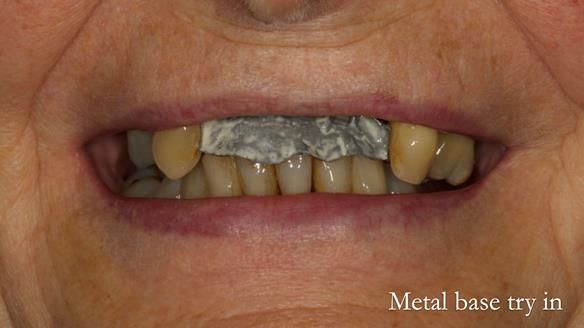

In this edition, I present the removable partial denture treatment for Jean, an 80-year-old woman with a sore mouth caused by a soft tissue-supported 'gum stripper' acrylic denture and a clenching habit. Below, I outline the step-by-step process of her treatment. It wasn't straightforward; I had to remake the denture after it fractured to achieve a satisfactory result. Each patient is unique, and sometimes a new RPD serves as a prototype. Occasionally, I need to make adjustments, learn from any mistakes, and refine the design to get it right.

The treatment has been a success over the past 4 years.